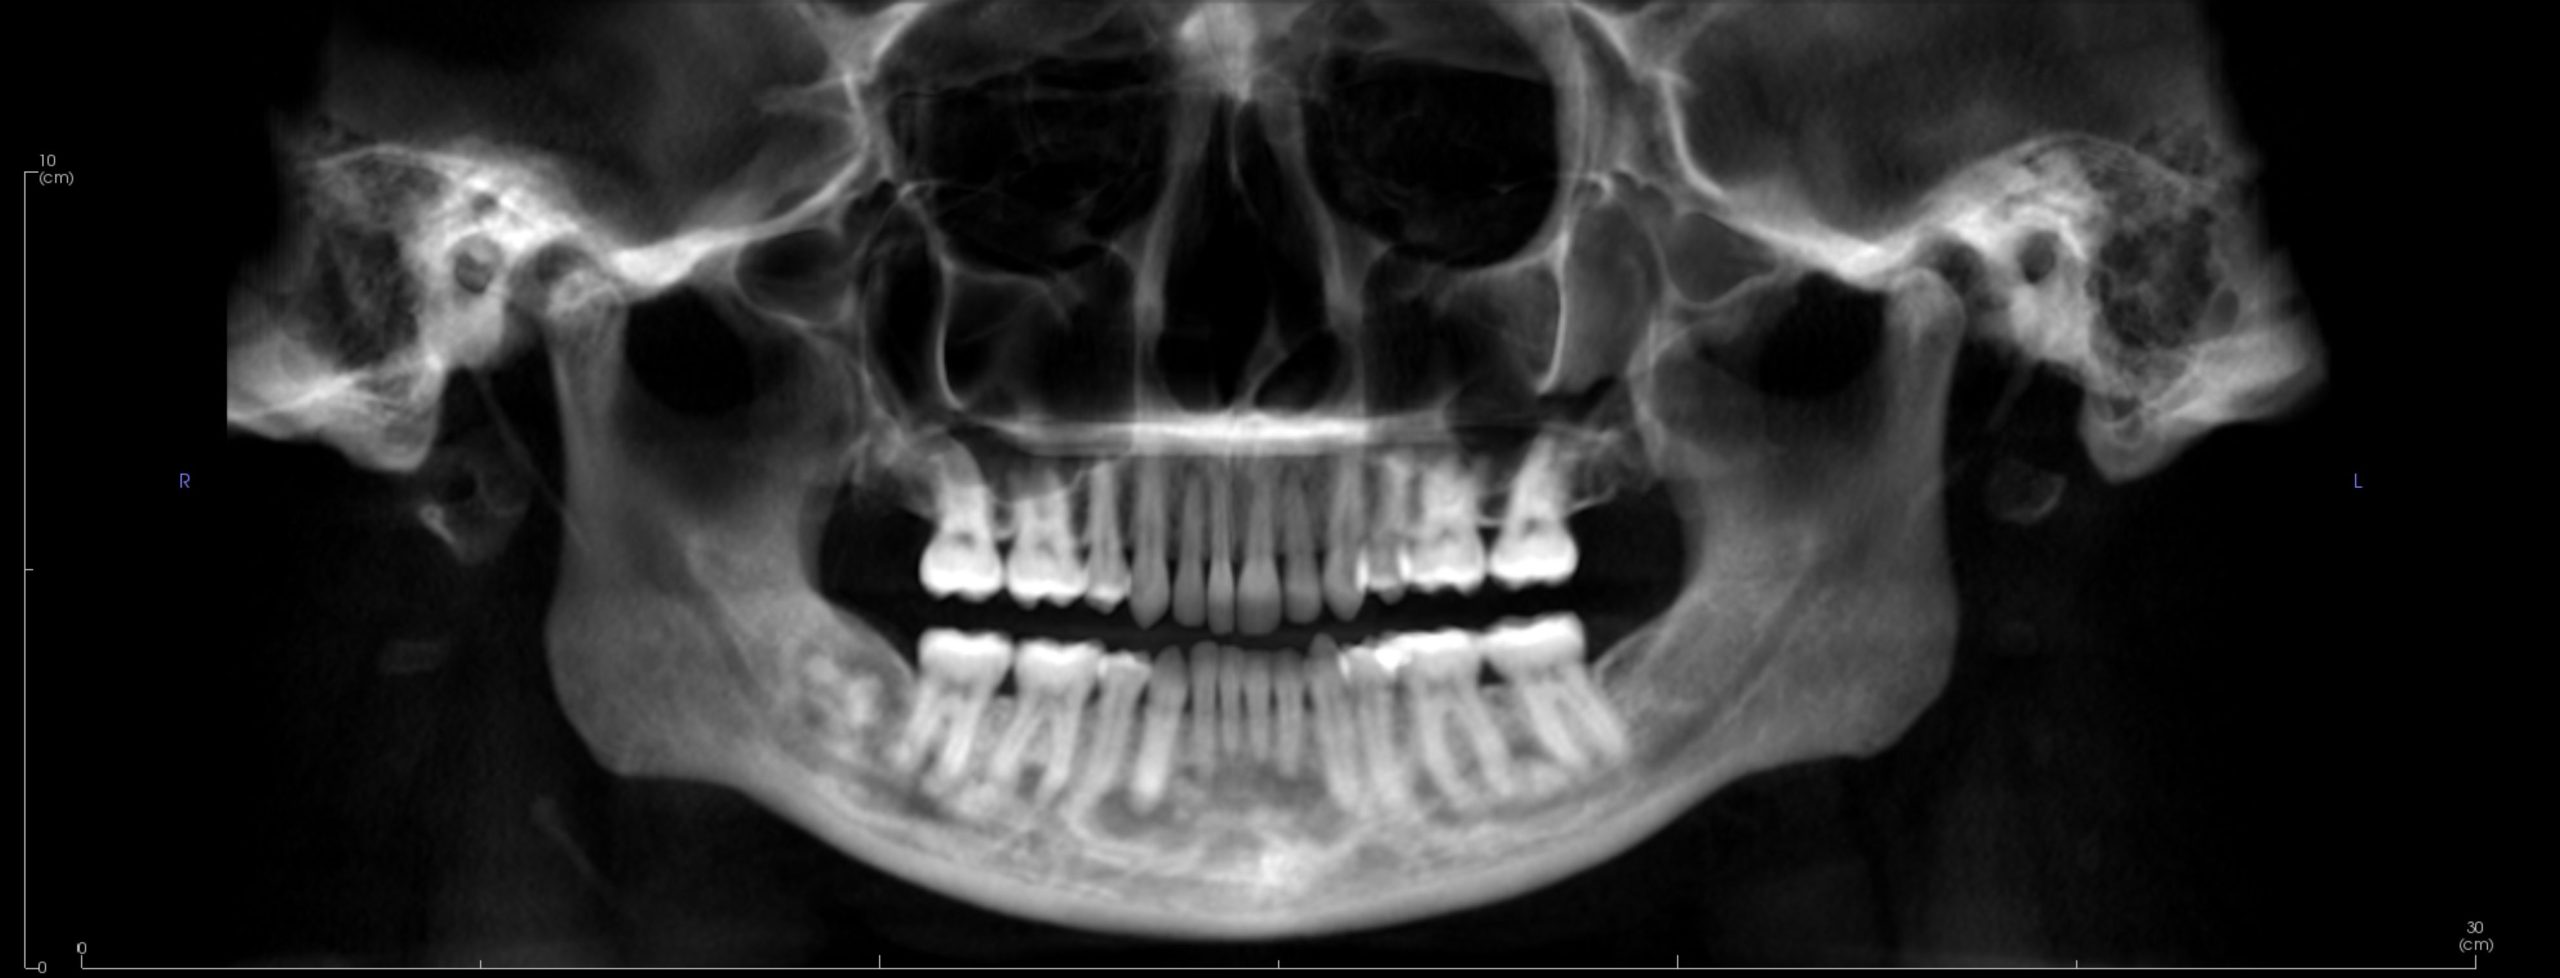

Image Portfolios visually communicate the imaging goals to you and your patient.